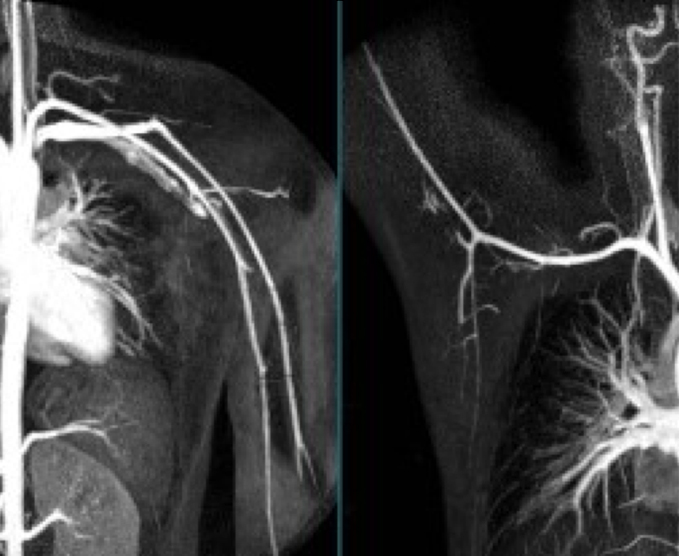

Angiotomografías

La angiografía por TC (ATC) combina una tomografía computarizada con la inyección de una tintura de contraste. TC significa tomografía computarizada. Esta técnica es capaz de crear imágenes de los vasos sanguíneos para detección de anomalías.

- Angiografía de MPS